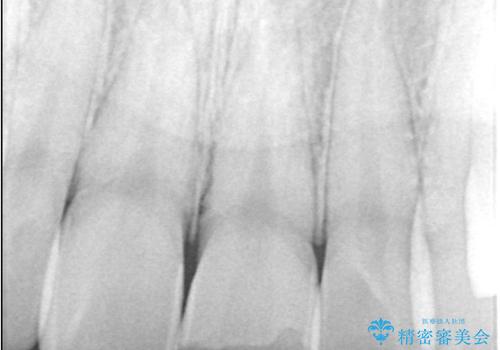

- 歯冠破折により点状露髄を認めました。破折から1週間以内であったこと、また歯髄診断により生活反応が良好で保存可能と判断したため、VPT(生活歯髄療法)を行い神経の保存を試みました。

神経の状態が良好に保たれていることを確認した後、オールセラミッククラウンによる審美修復を行いました。